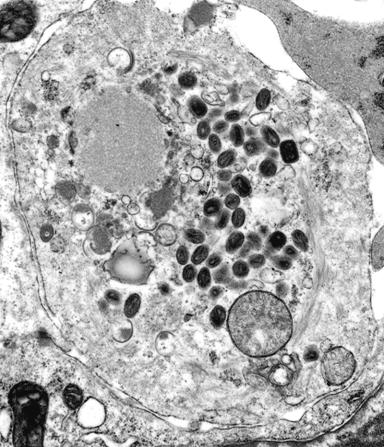

羊瘙痒病发现已有200年的历史,羊得了这种病就会浑身发痒,不断在坚硬物质上搓擦身体,最后死亡。它是一类传染性海绵状脑病(transmissible spongiform encephalopathies,TSE)。疯牛病,即牛海绵状脑病(bovine spongiform encephalopathy,BSE)也属于此类疾病,发现于1986年,是由于牛被喂以由死羊骨粉制造的饲料而被感染,病牛脑内灰质及神经元都有典型的海绵状退化(图3-27、28),出现淀粉样(amyloid)蛋白沉淀(图3-28),与羊瘙痒病相似。同类型的prion也会使鹿、貂及猴子患病,人类也具有类似的疾病。

图3-28

vCJD病人大脑组织切片,左、海绵状病变及周围的沉淀斑,右、淀粉样蛋白沉淀,短线表示50um。引自Stanley B. Prusiner 1997